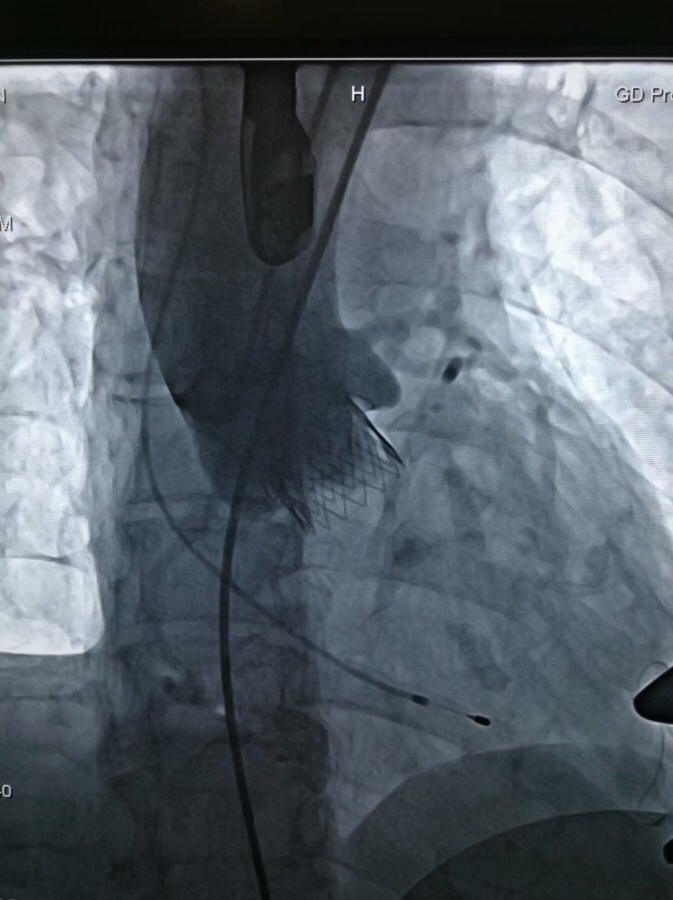

图片说明:人工瓣膜释放完成。

术中,在TAVI心脏手术团队的协作下,首先在患者心尖部位开一小孔,然后操控一根细长的输送鞘,将人工生物心脏瓣膜送入患者心腔。在造影屏幕监视下,新瓣膜被准确定位和放置于病变主动脉瓣位置。原来的心脏泵血“阀门”因关不紧“漏水”,新瓣膜“安装”完毕后,就像一扇运行良好的新“阀门”,一张一合地开始工作了。

整个手术过程非常顺利,仅耗1个半小时,胸骨肋骨无任何破坏,也无需体外循环,出血量未超过100ml。术后2小时老太太完全清醒过来并拔除气管插管,还能与医务人员轻松交谈。